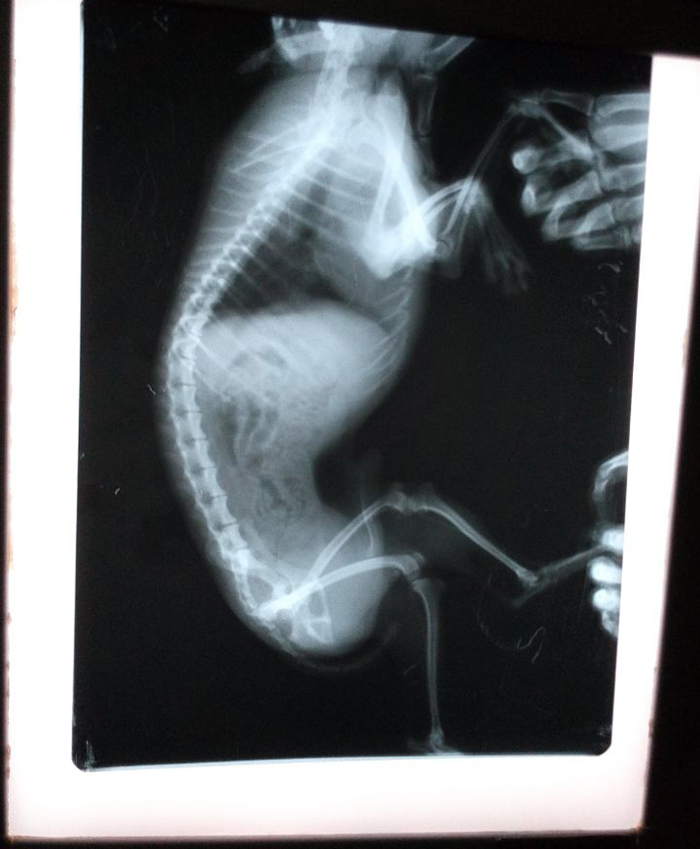

洛阳市洛龙区澳科动物医院

澳科动物医院